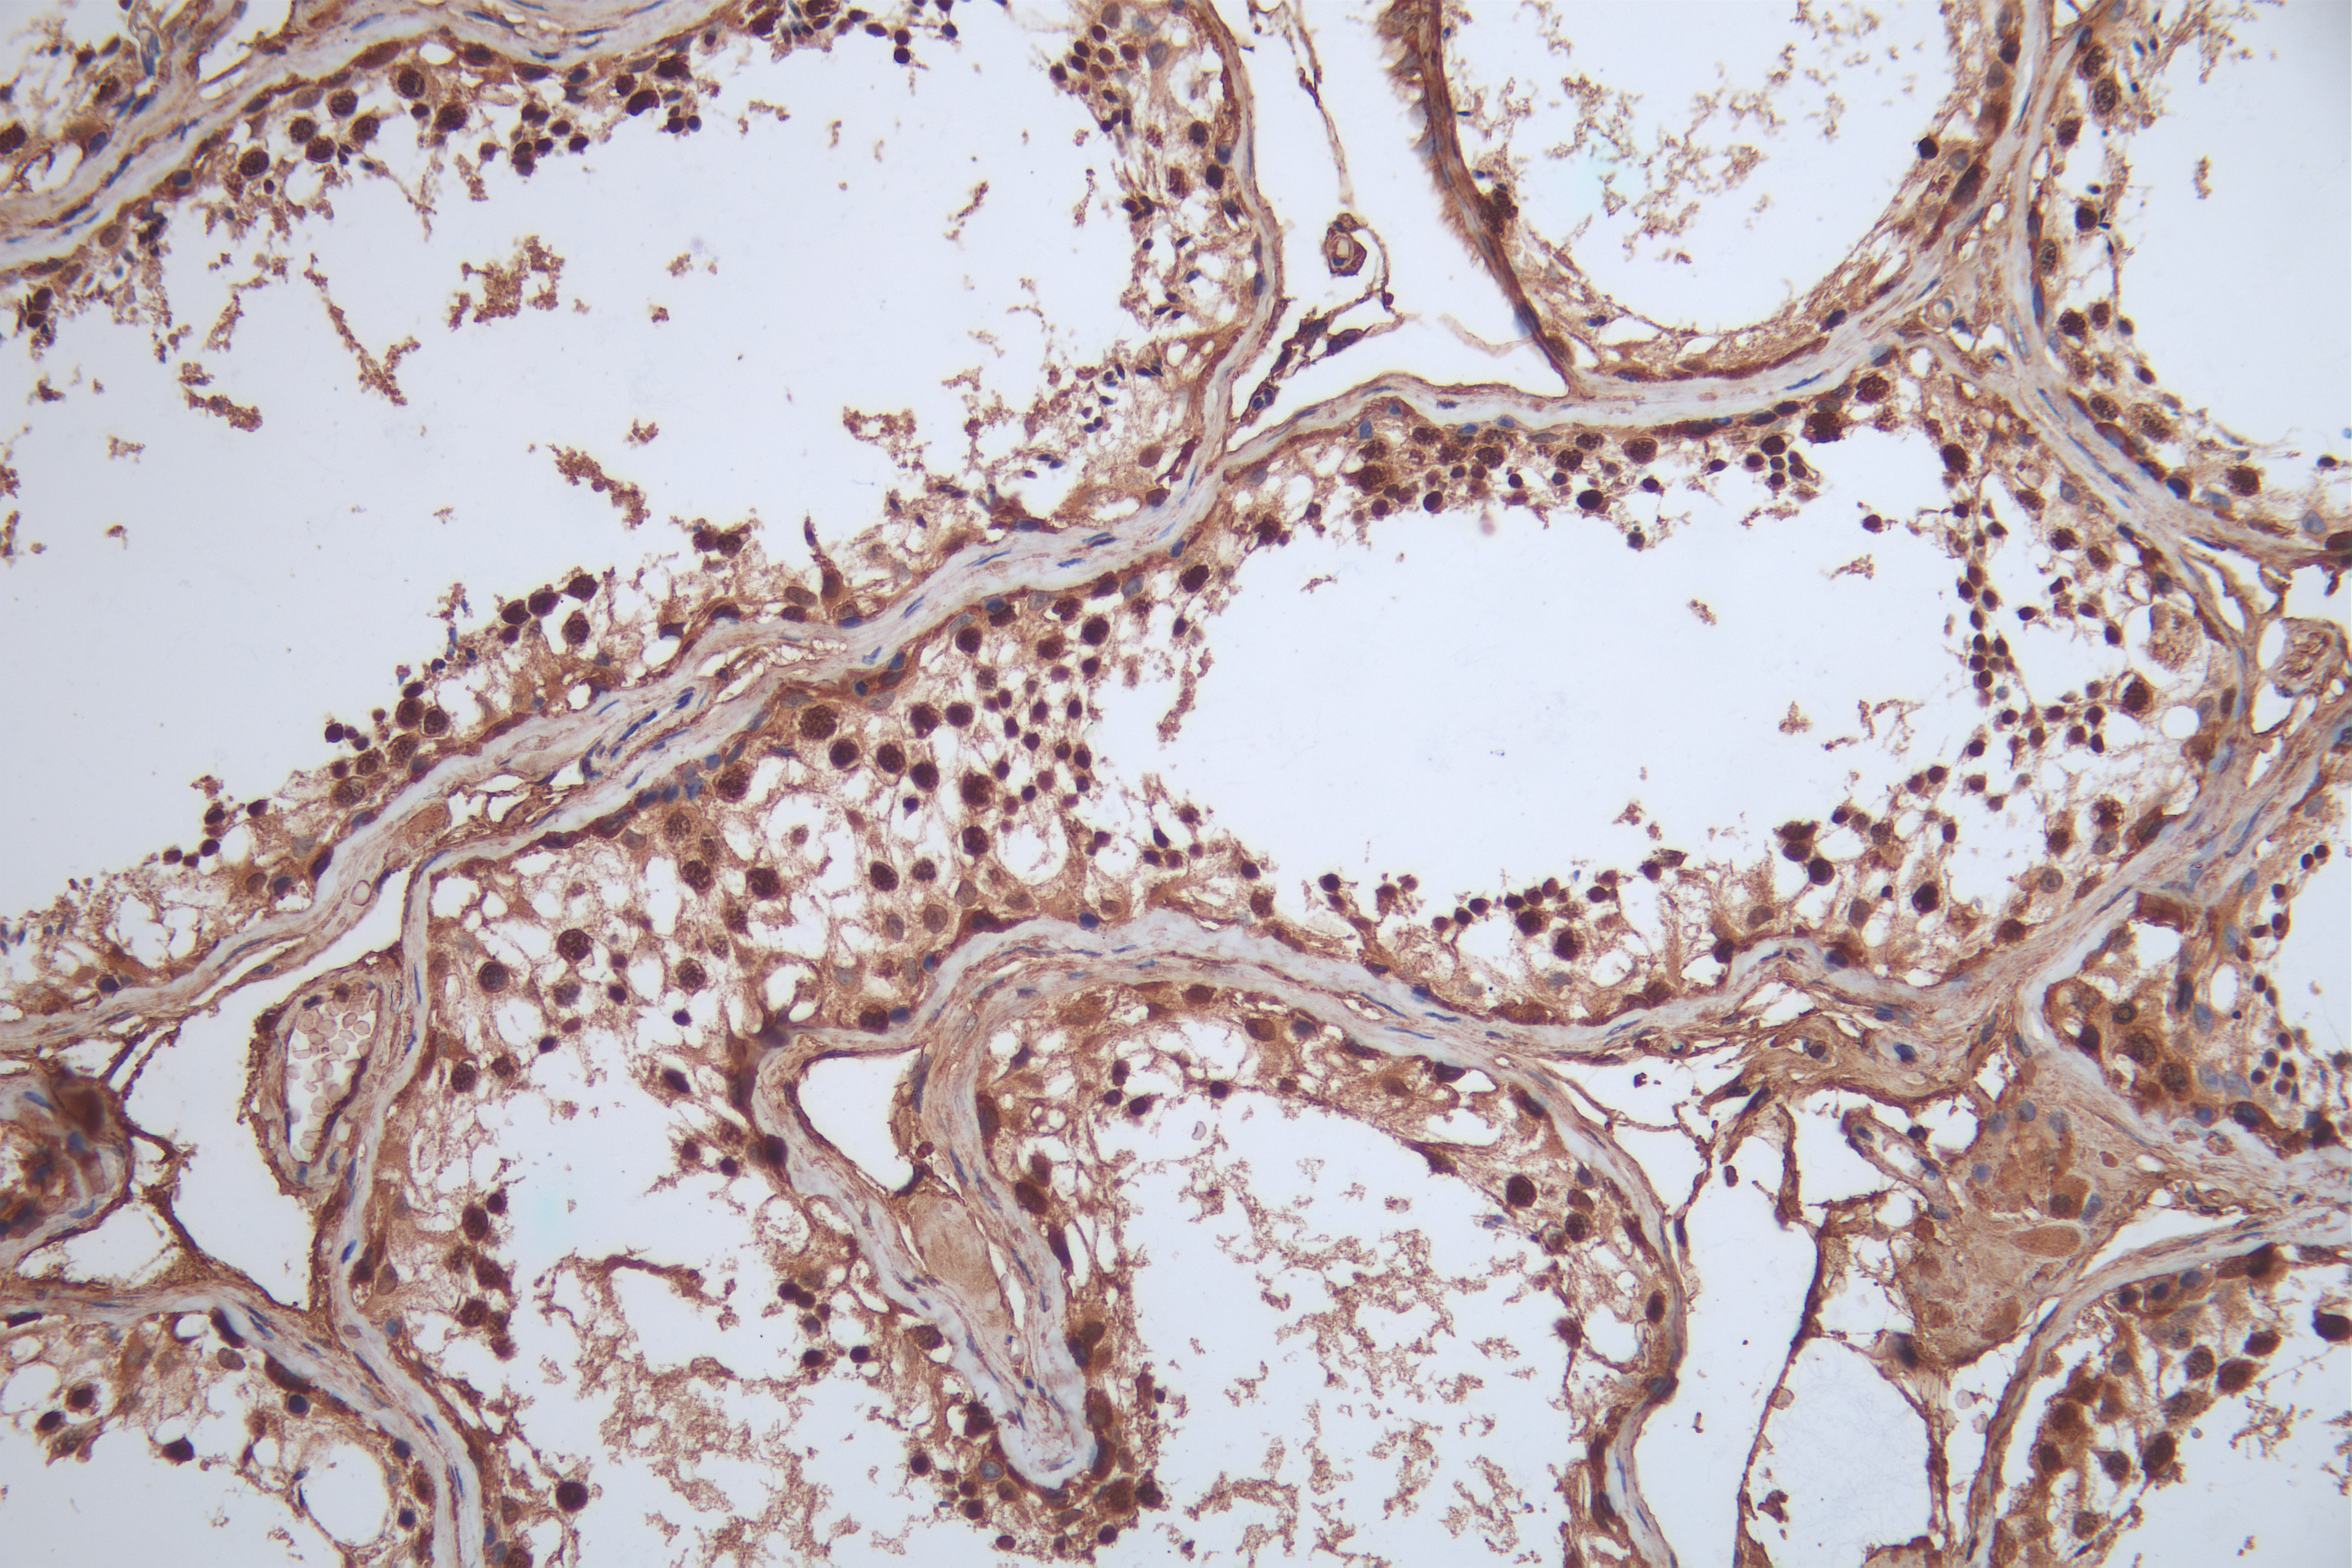

IHC image of CSB-RA904894A0HU diluted at 1:100 and staining in paraffin-embedded human testis tissue performed on a Leica BondTM system. After dewaxing and hydration, antigen retrieval was mediated by high pressure in a citrate buffer (pH 6.0). Section was blocked with 10% normal goat serum 30min at RT. Then primary antibody (1% BSA) was incubated at 4°C overnight. The primary is detected by a Goat anti-rabbit polymer IgG labeled by HRP and visualized using 0.05% DAB.